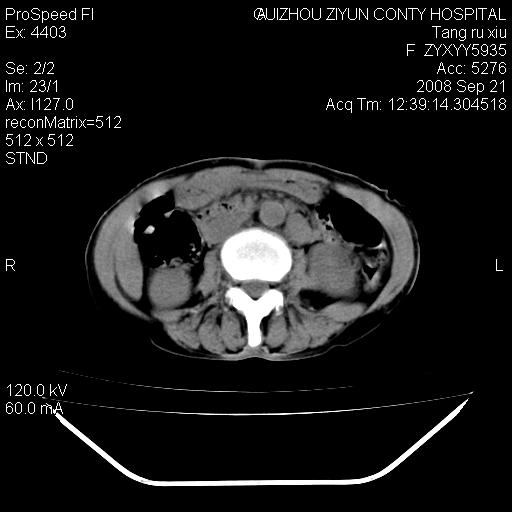

f、57岁,上腹痛.2月,近来胸闷。2月前在外院摄胸片示左侧胸腔少量积液。

(患者腹痛入院,欲吐,临床医生说禁饮,所以没有口服对比剂)

肝脏大小形态尚可,其实质内可见多发大小不等的低密度影,边缘模糊。肝门区结构紊乱,腔静脉腹主动脉旁可见多发软组织密度影,部分融合成团块状,并向下延伸。胰腺及十二指肠结构显示不清。腹腔内脐后肠管走形僵硬,管壁可见增厚。盆腔内可见多个淋巴结影。所扫层面左侧胸腔可见大量弧形水样密度影,其内侧可见被压缩的肺组织影。左侧胸壁可见一小结节样软组织密度影,边缘模糊。心脏纵隔向右侧移位。心脏包膜内可见囊样低密度影,其内侧心房室周围可见一圈气体样密度影。纵隔内大血管旁可见多发软组织团块影,部分融合。

1.腹膜后淋巴瘤侵及肝脏,肺内及纵隔内多发转移。2.左侧大量胸腔积液并压缩性肺不张。3.心包脓肿可能,转移不除外。4.脐后局部肠管管壁增厚,考虑炎症可能,肿瘤不除外。